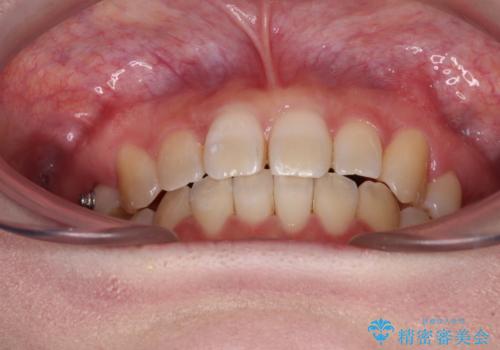

ディープバイトをインビザライン矯正で改善

インビザラインを用いて、前歯の叢生を解消するとともに、ディープバイトを改善していくこととしました。

上顎に乳歯が左右1本ずつ残っていたため、若干咬み合わせに不具合が残りましたが、強い咬合力の原因であったディープバイトをしっかりと改善することができました。